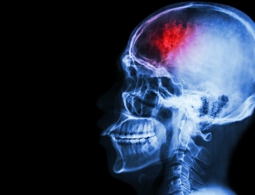

Инсульт на молекулярном уровне: что повреждается в результате удара

Инсульт в настоящее время является главной проблемой неврологии и занимает второе место в мире в списке причин смертности среди населения. Работа над предотвращением его последствий ведется во многих лабораториях мира. Во Всемирный день борьбы с инсультом, 29...